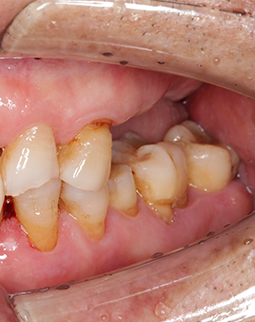

我做过活动牙,为了给孩子省钱,吃饭的时候含着假牙不敢咀嚼,因为活动牙脱落过,差点就误吞了,我每天带着小孙子玩,小孙子总觉得我口臭不让我亲…每天摘下来的时候小心翼翼,怕挂钩勾伤牙龈,看看我这被活动牙挂钩勾出来的沟壑。我们那个年代的人,节衣缩食成习惯了,左邻右里听说我要种牙,议论声一片,好像总觉得老人家就应该为家为孩子,继续隐忍付出,其实,我们也能有晚年的春天,能想吃就吃,能健健康康。

缺了8颗牙,名副其实的“缺牙一颗带坏全口”,在检查后,我右边的第一缺牙已经有严重的骨萎缩了,是“纸片骨”,种牙难度很大,我从湖南跑到深圳,可以说一路都在对比医院和方案。